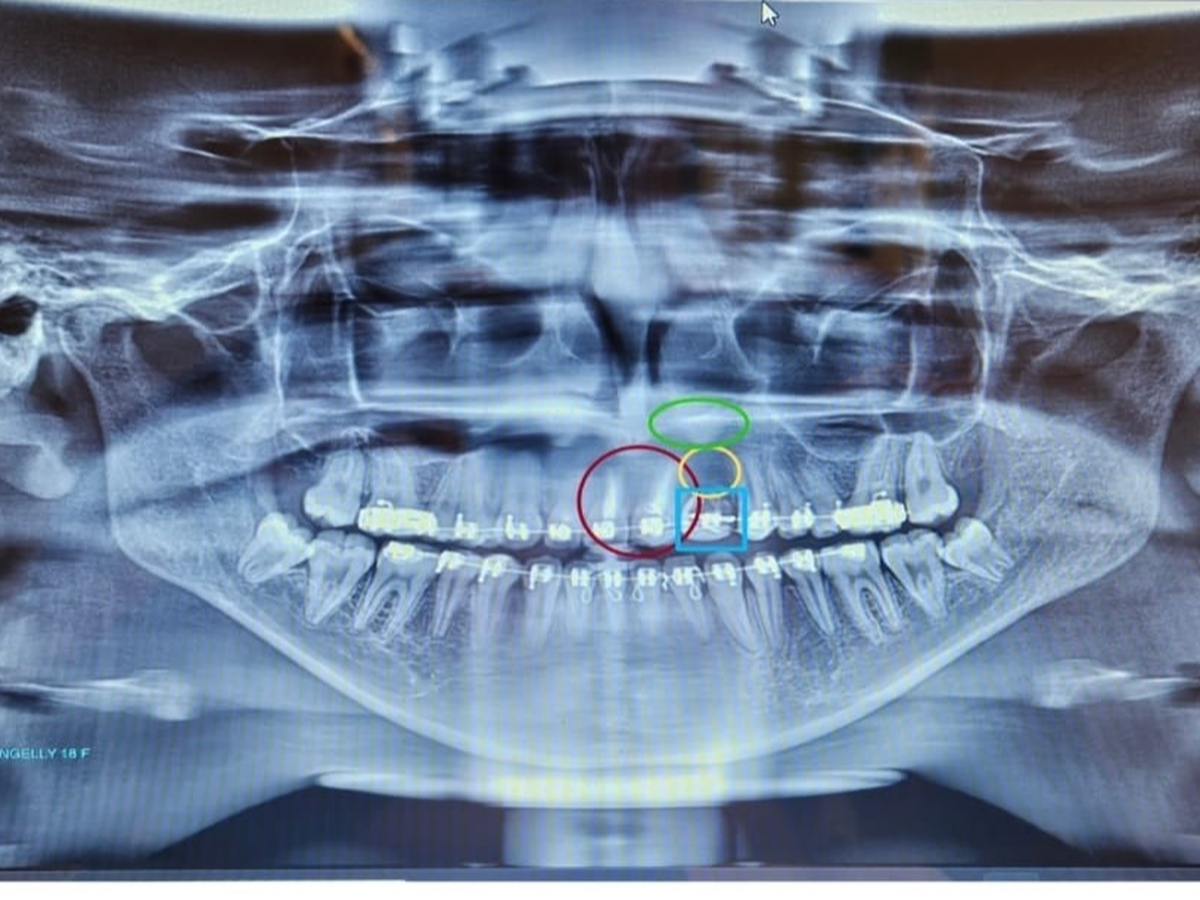

Hoy, con sus 18 años recién cumplidos, Liangelly finalmente puede someterse a los procedimientos médicos y dentales que necesita. Pero el tiempo ha pasado factura, y ahora enfrenta una serie de tratamientos complejos y costosos, incluyendo reconstrucción dental, injertos óseos y prótesis permanentes, además tiene un quiste y un abseso sobre un diente al cual se le realizó una biopsia y estamos en espera de los resultados.

Evaluaciones especializadas y radiografías 3D